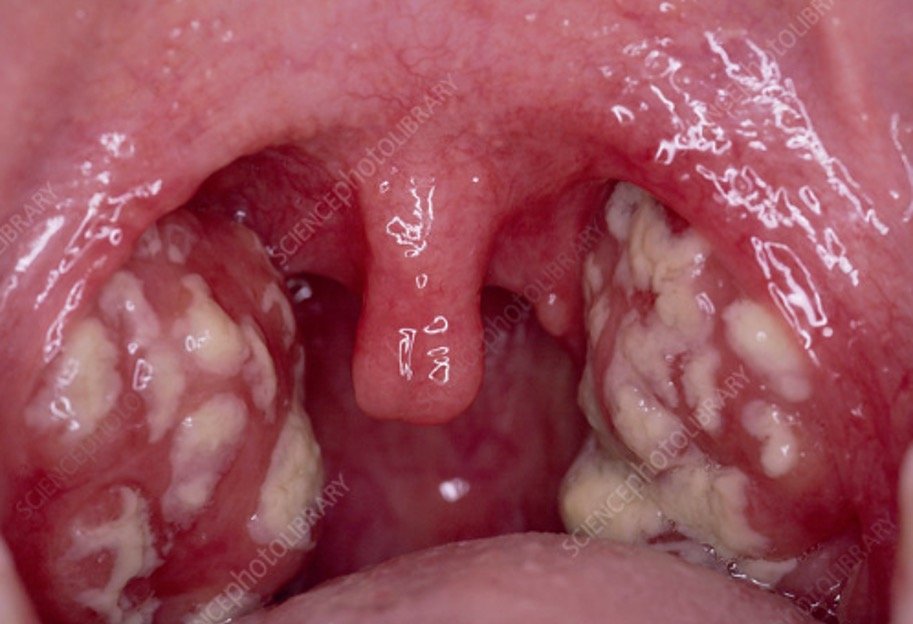

Тонзиллит

Тонзиллит — это воспаление миндалин, вызванное вирусными или бактериальными инфекциями. Симптомы тонзиллита включают боль в горле, затруднение при глотании, лихорадку и увеличение миндалин.